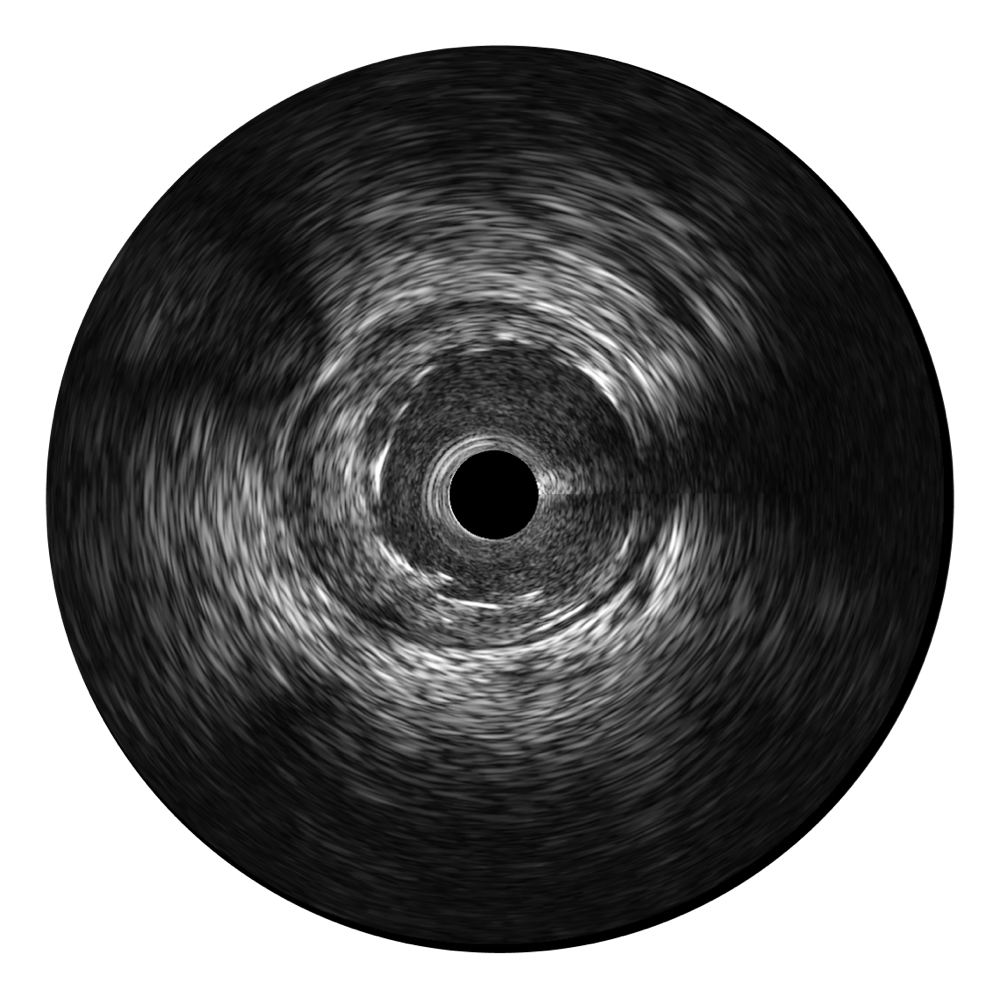

• 百老汇电子游戏官网宽频IVUS图像

• 传统IVUS图像

对比传统IVUS导管成像,百老汇电子游戏官网宽频IVUS图像的近场支架梁显影更细腻,远场中膜外血管仍清晰可辨,兼顾远中近,兼顾分辨力与穿透深度